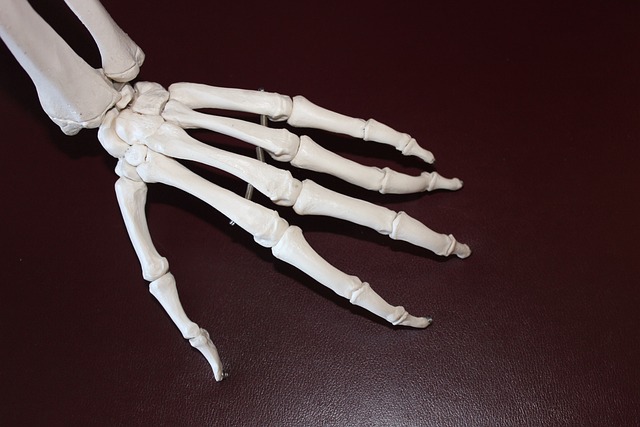

골관절염은 관절의 연골이 마모되어 발생하는 퇴행성 질환으로, 주로 무릎, 손, 엉덩이, 척추 관절에서 발생하며, 통증, 부종, 운동 범위 감소 등의 증상을 유발합니다. 콘드로이친은 이러한 골관절염의 증상을 완화하는 데 도움을 줄 수 있는 것으로 알려져 있습니다.